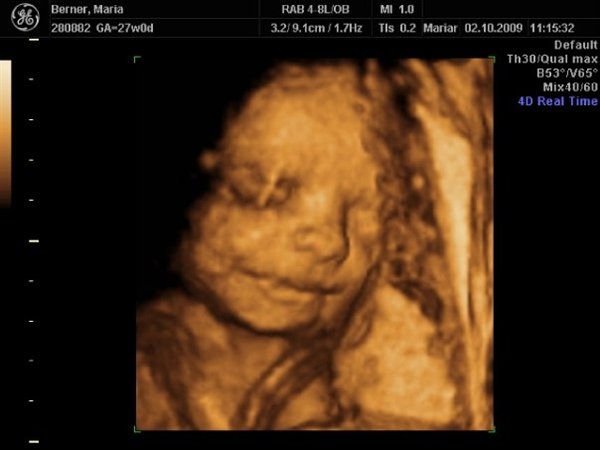

Men vi fik nogle dejlige billeder af Dicte som dog lå og puttede ansigtet ind i livmodervæggen, så det gjorde det lidt svært at få de helt skarpe billeder. Hun var 928 gram, og deres udregning af termin siger også 1. januar

Det er 3. gang nu en scanning har sagt det.